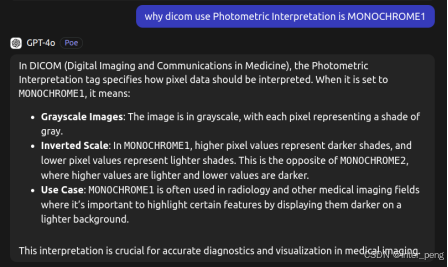

但后来通过询问GPT, 才了解到,这其实可能是故意为之的.

GPT给出的回答是:对于某一些传统的显示设备,或专家,他们更习惯来看,就是用白色代表密度低,黑色代表密度高的片子. 因此,在拍摄的时候,设备才会这样而为之.